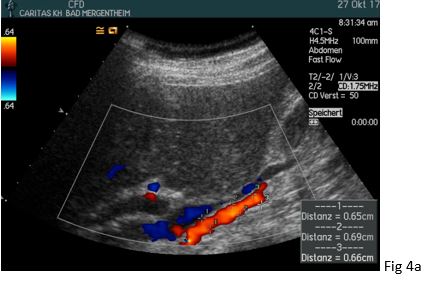

Figure 4:(a) A normal and low-resistance Doppler spectrum was demonstrated one day after dilatation of the right renal artery (in between markers) without a bruit and turbulence.

(b) There was a PSV/EDV of 103/43 cm/s (RI = 0.59) (AO: aorta). .